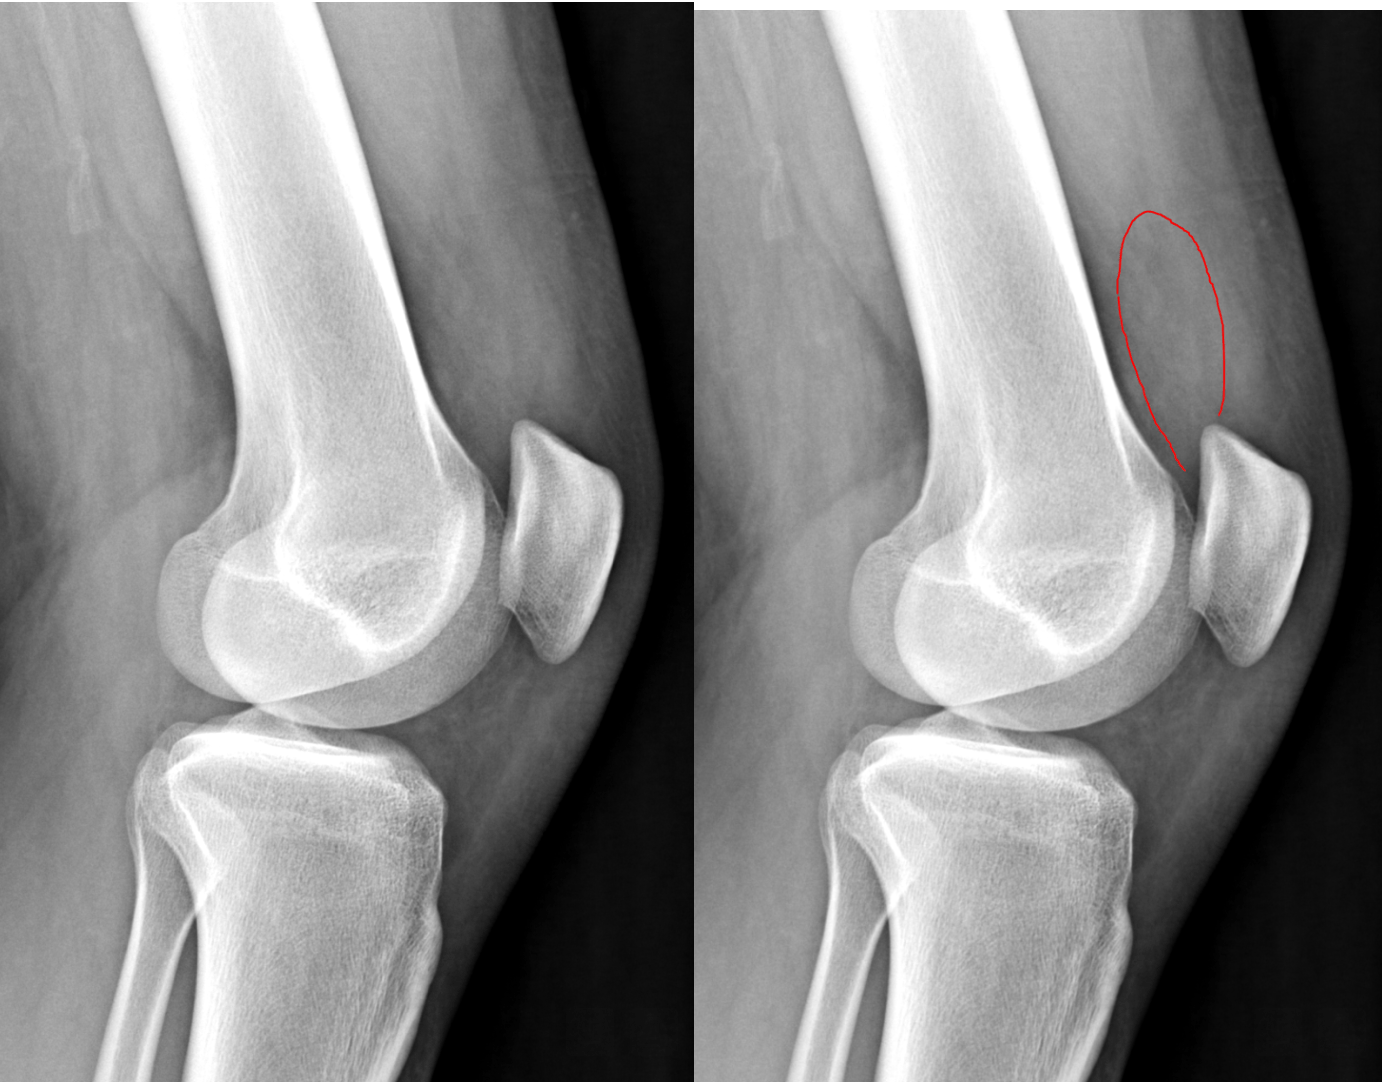

Musculoskeletal (MSK) Xray Interpretation OSCE Guide Geeky Medics Large Size Knee Joint Effusion There are certainly other signs of knee joint effusions such as anterior displacement of the patella, but these are only reliably seen on large. Four major ligaments support the knee, which is the largest. A knee effusion refers to an abnormal fluid accumulation within the knee joint. Joint effusion is swelling of the tissues in or around your joint because. Large Size Knee Joint Effusion.

Right knee radiograph with joint effusion (star) and soft tissue Large Size Knee Joint Effusion Joint effusion can cause a puffy appearance to your joints along with symptoms like pain and. Common causes include arthritis and injury to knee. Knee effusion, sometimes called water on the knee, occurs when excess fluid accumulates in or around the knee joint. Swelling and fluid around your joint can be. Knee effusions can arise from traumatic injuries, such as. Large Size Knee Joint Effusion.

kneejointeffusion Don't the Bubbles Large Size Knee Joint Effusion There are certainly other signs of knee joint effusions such as anterior displacement of the patella, but these are only reliably seen on large. Joint effusion can cause a puffy appearance to your joints along with symptoms like pain and. Common causes include arthritis and injury to knee. Knee effusion, sometimes called water on the knee, occurs when excess fluid. Large Size Knee Joint Effusion.